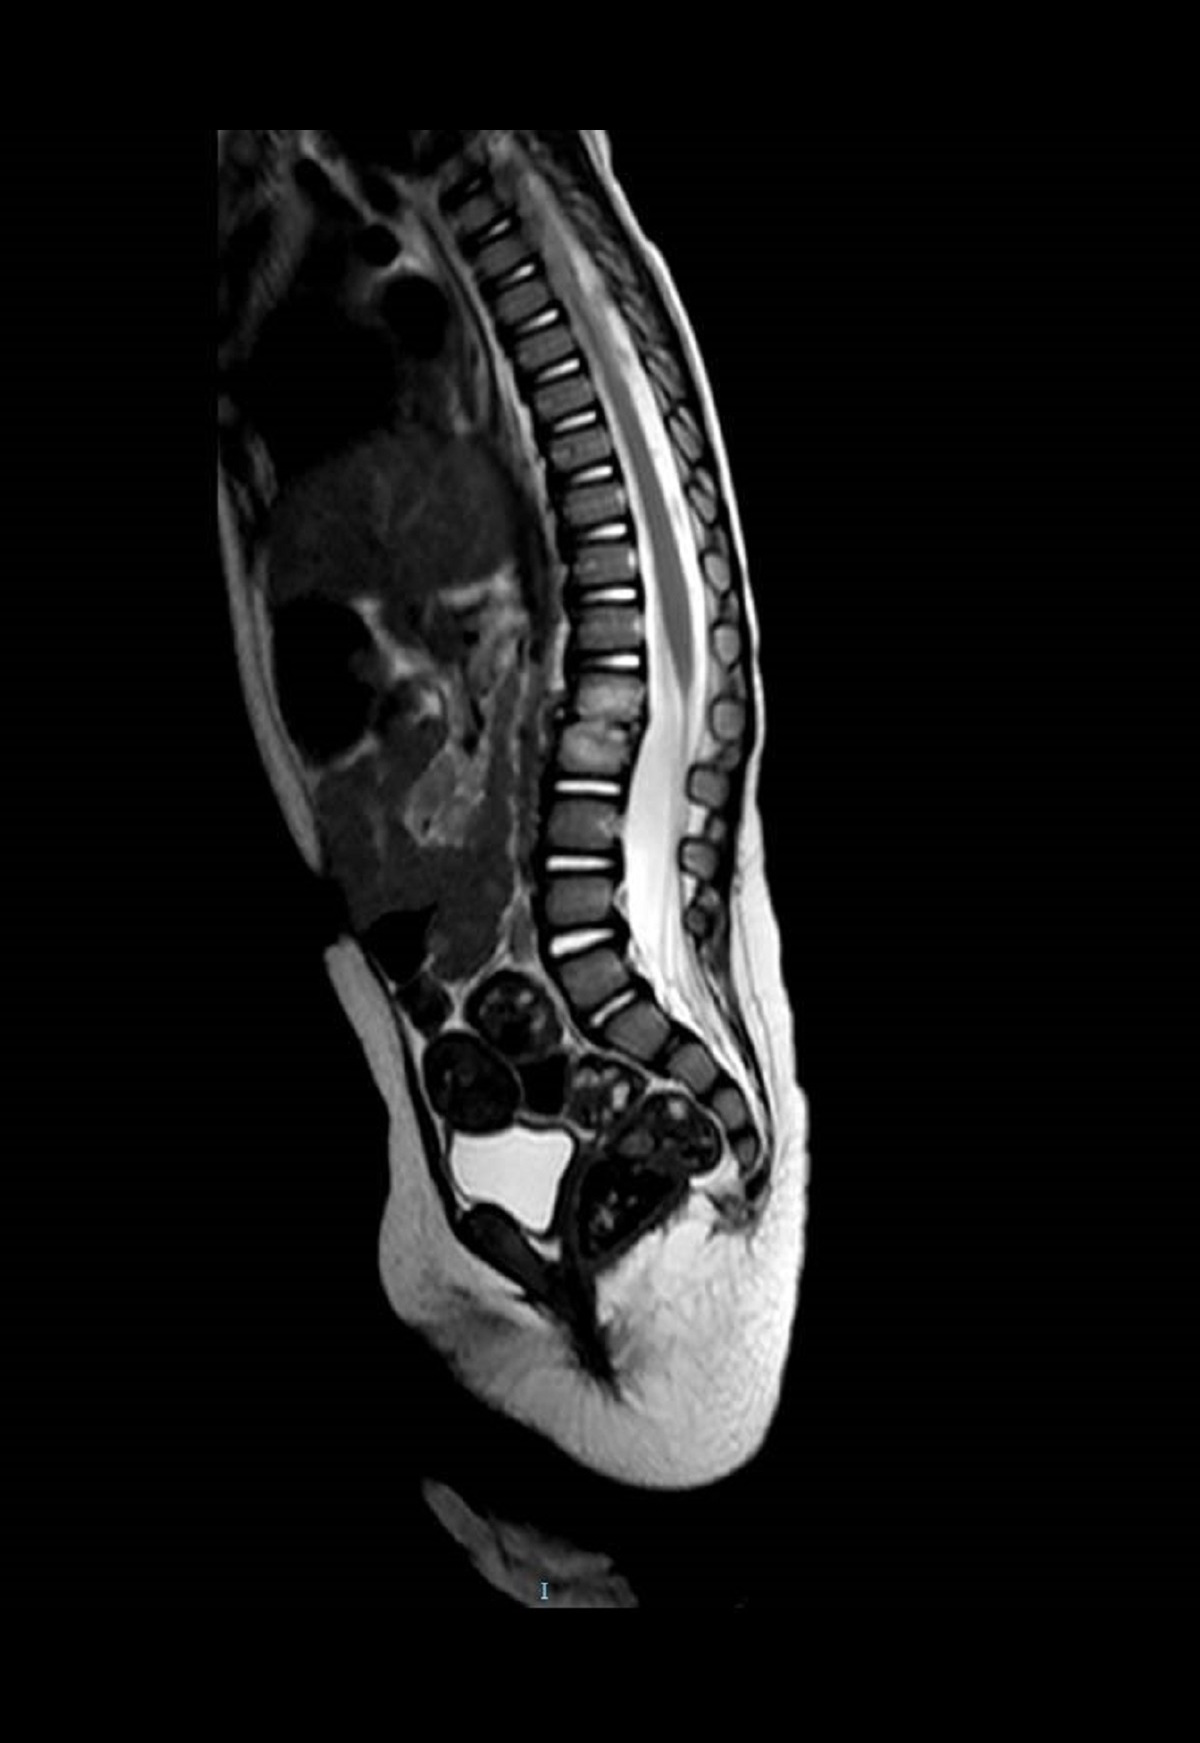

Niña de 15 meses, sin antecedentes médico-quirúrgicos de interés, que acude por irritabilidad, rechazo de deambulación y sedestación de 2 semanas de evolución asociado a estreñimiento de 4 días. Afebril en todo momento. A la exploración destaca dolor a la palpación en apófisis espinosas lumbares. A la deambulación adopta una postura antiálgica con hiperlordosis. Se practica radiografía lateral de columna (Figura 1) y RNM con contraste i.v. (Figura 2).

Figura 2. RNM con contraste i.v. de la columna dorsolumbar en la que se aprecia pérdida en la altura del interespacio L1-L2 con cambios en la intensidad de la señal de ambos cuerpos vertebrales con intensidad de señal baja en T1 y alta en T2, y una captación de contraste generalizada que presenta una mayor prominencia a nivel del interespacio (disco).